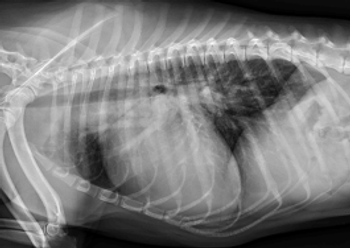

In the spirit of “building a better mousetrap,” researchers have tested a novel measurement protocol—the manubrium heart score—for flagging cardiac disease in dogs.